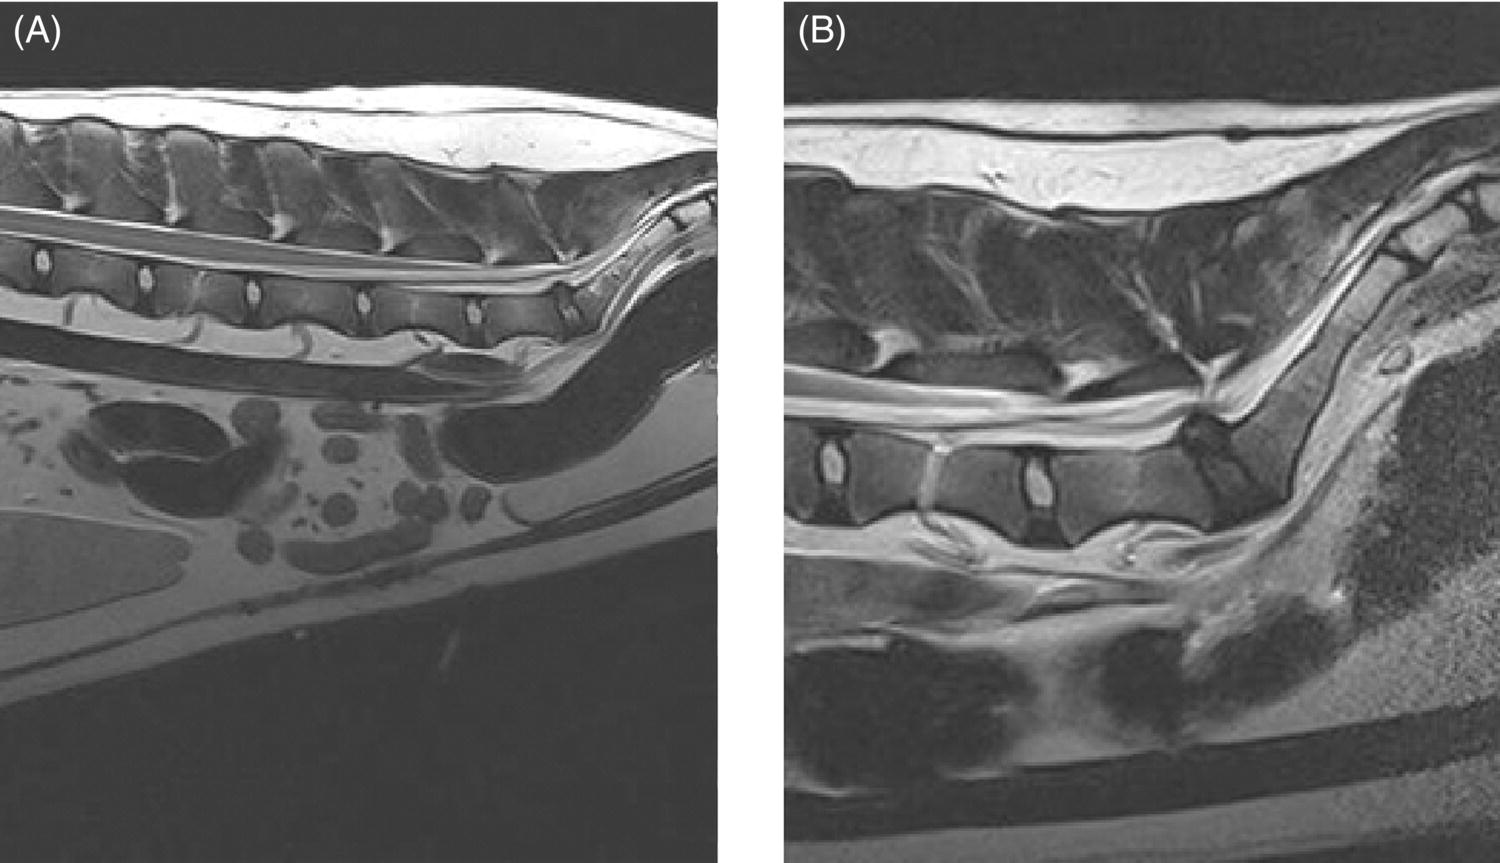

From veteriankey.com

Lumbosacral Disc Disease Veterian Key Lumbar Disc Disease Dogs Stage iii disc disease causes partial paralysis. Intervertebral disc disease in dogs refers to a ruptured, displaced, or herniated disc in their back. This condition is most commonly seen in beagles, dachshunds,. Intervertebral disk disease (ivdd) in dogs can also be described as a ruptured, slipped, bulging or herniated disk. Intervertebral disc disease (ivdd) is a common source of back. Lumbar Disc Disease Dogs.